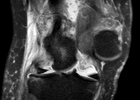

近日,我院妇科成功完成一例“巨大子宫肌瘤切除术+子宫切除术”,子宫肌瘤手术成功案例在我院数不胜举,然而像这么大的子宫肌瘤确实较为罕见。 李女士因腰痛伴尿频1天来我院就诊,入院体查时妇科医生发现,李女士腹部膨隆如一足月孕产妇,盆腔核磁提示包块大小约137x102x204mm,膀胱受压。接诊医生考虑子宫肌瘤,以“...2024-12-27